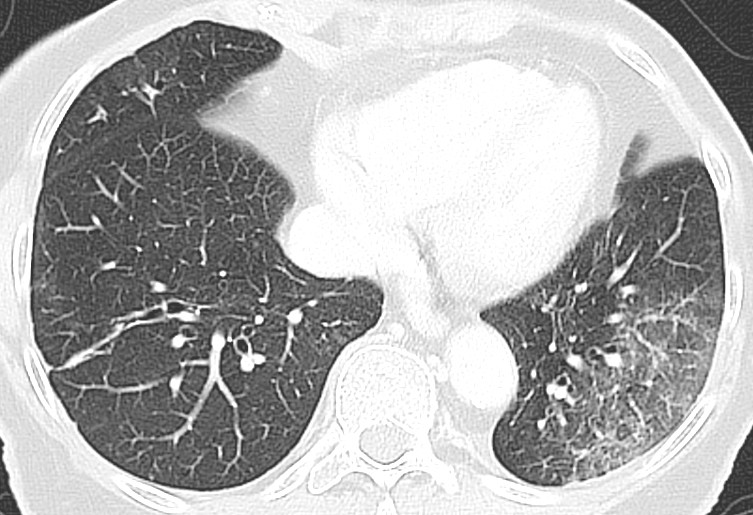

Typiske CT-funn varierer med symptomvarighet og kan deles i tre stadier: en tidlig fase, en intermediær fase som strekker seg fra 3–5 dager etter symptomdebut, og en senfase. Det er ikke alltid funn på CT de første dagene etter symptomdebut. I et materiale med symptomatiske, men uspesifiserte pasienter hadde 56 % normale funn på CT innen to dager etter symptomdebut (12), avtakende til 9 % 3–5 dager etter symptomdebut og 4 % 6–12 dager etter symptomdebut. Funnhyppighet varierer med sykdommens alvorlighetsgrad. Ved første gangs bildediagnostikk var det normale funn hos 18 % i en gruppe pasienter med ikke alvorlig sykdom, men hos bare 3 % av pasienter med alvorlig sykdom (15). Typiske CT-funn er multiple, bilaterale mattglassfortetninger med perifer distribusjon, hyppigst lokalisert i underlappene. I intermediær fase er det økende innslag av konsolidering (tette infiltrater) og affeksjon av flere lapper samt økt septering med brosteinsmønster (crazy paving) som tegn på interstitiell affeksjon. I senfasen er det økende total utbredelse, men mattglassfortetninger og konsolidering er fremdeles dominerende funn (12, 16). Figur 4, figur 5 og figur 6 viser typiske funn på CT i ulike faser av covid-19.

Ved alvorlig sykdomsforløp kan det påvises distorsjon av lungearkitekturen, traksjonsbronkiektasier, forstørrede lymfeknuter og pleuravæske. Dette er funn som ikke er spesifikke for covid-19 (17).